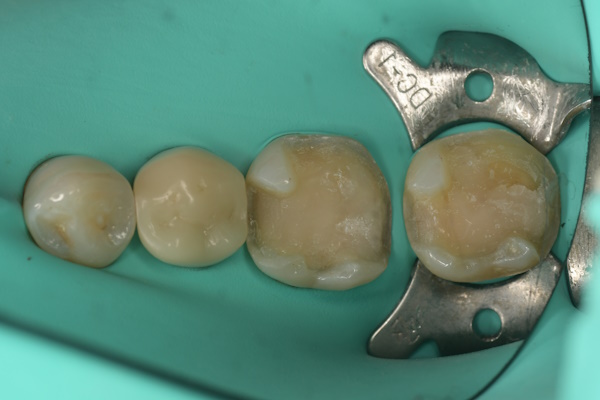

セラミック治療の治療例です。歯科治療に対する強い恐怖心があり、これまで継続的な通院が難しい状態でした。臼歯部には過去の治療歴があり、詰め物の下から虫歯が再発している状態(二次カリエス)が認められました。当院にて、患者様の不安を軽減するため静脈内鎮静法を併用し、2本同時に虫歯を除去したうえで、同日にセラミックによる修復を実施しました。接着効率を高めるため、ラバーダムを使用しています。オキシガードは、過酸化物と還元剤による化学重合反応により、歯科接着用レジンセメント表面の未重合層を硬化させる材料です。さらに、未重合層を空気から遮断することで、確実な硬化を促します。

虫歯処置後